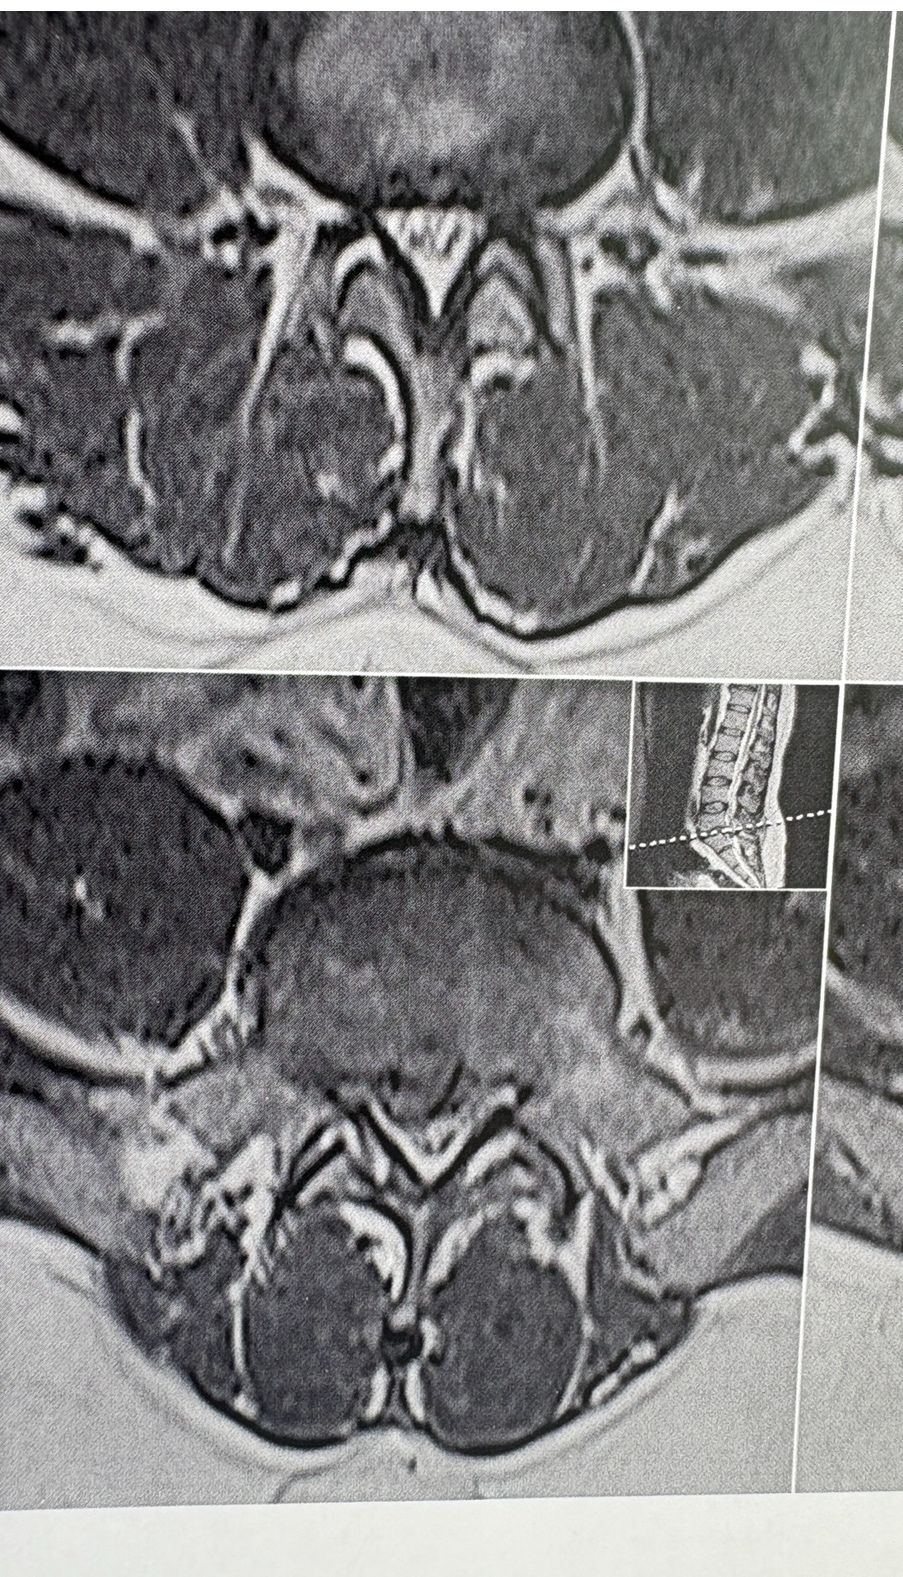

MRIs before and after proper management of this patient:

41 years old man presented to my clinic in October 2023 with acute and sever R neck pain with radicular pain to his R upper extremity along C6 dematom since 2 weeks ago. Examination didn’t show any upper motor signs. Was suggested urgent surgery

I ordered EMG/ NCV : showed mild R C6, C7 irritation without any active axonal loss

In his MRI was reported R. para R. IVF Massive extrusion. I decided to control his pain and manage this patient with reevaluation of patient every other session. For 5 sessions i just used acupuncture and laser and IFC and mild adjustments to his R. T3-T7 and mild arthosteem to above and below involved segment. Cervical adjustment considered contraindicated for this patient. From session 6th- 8th i started to use mild/gentle cervical decompression. He used soft cervical collar all the time. His pain decreased by 80 percent

I gave him cervical traction pump to be used 3-5 times per day at home for the next 3 months and i released the patient. He was evaluated every week once for one month and after that every 2 weeks. After 3 month I repeated MRI. Size of the herniated disc was reduced greater than 50 percent. Asked him to do another mri in 6 months

In general: Precise selection of the patients, examination,diagnosis, plan of management, reevaluation and treatment can be done by doctors of chiropractic for the patients with spinal disc herniation and stenosis Moreover giving reasonable time to these kind of patients under direct supervision by their chiropractic doctors can prevent unnecessary surgery. Proper selection of these kind of patients is another important fact that can be done precisely by chiropractors.